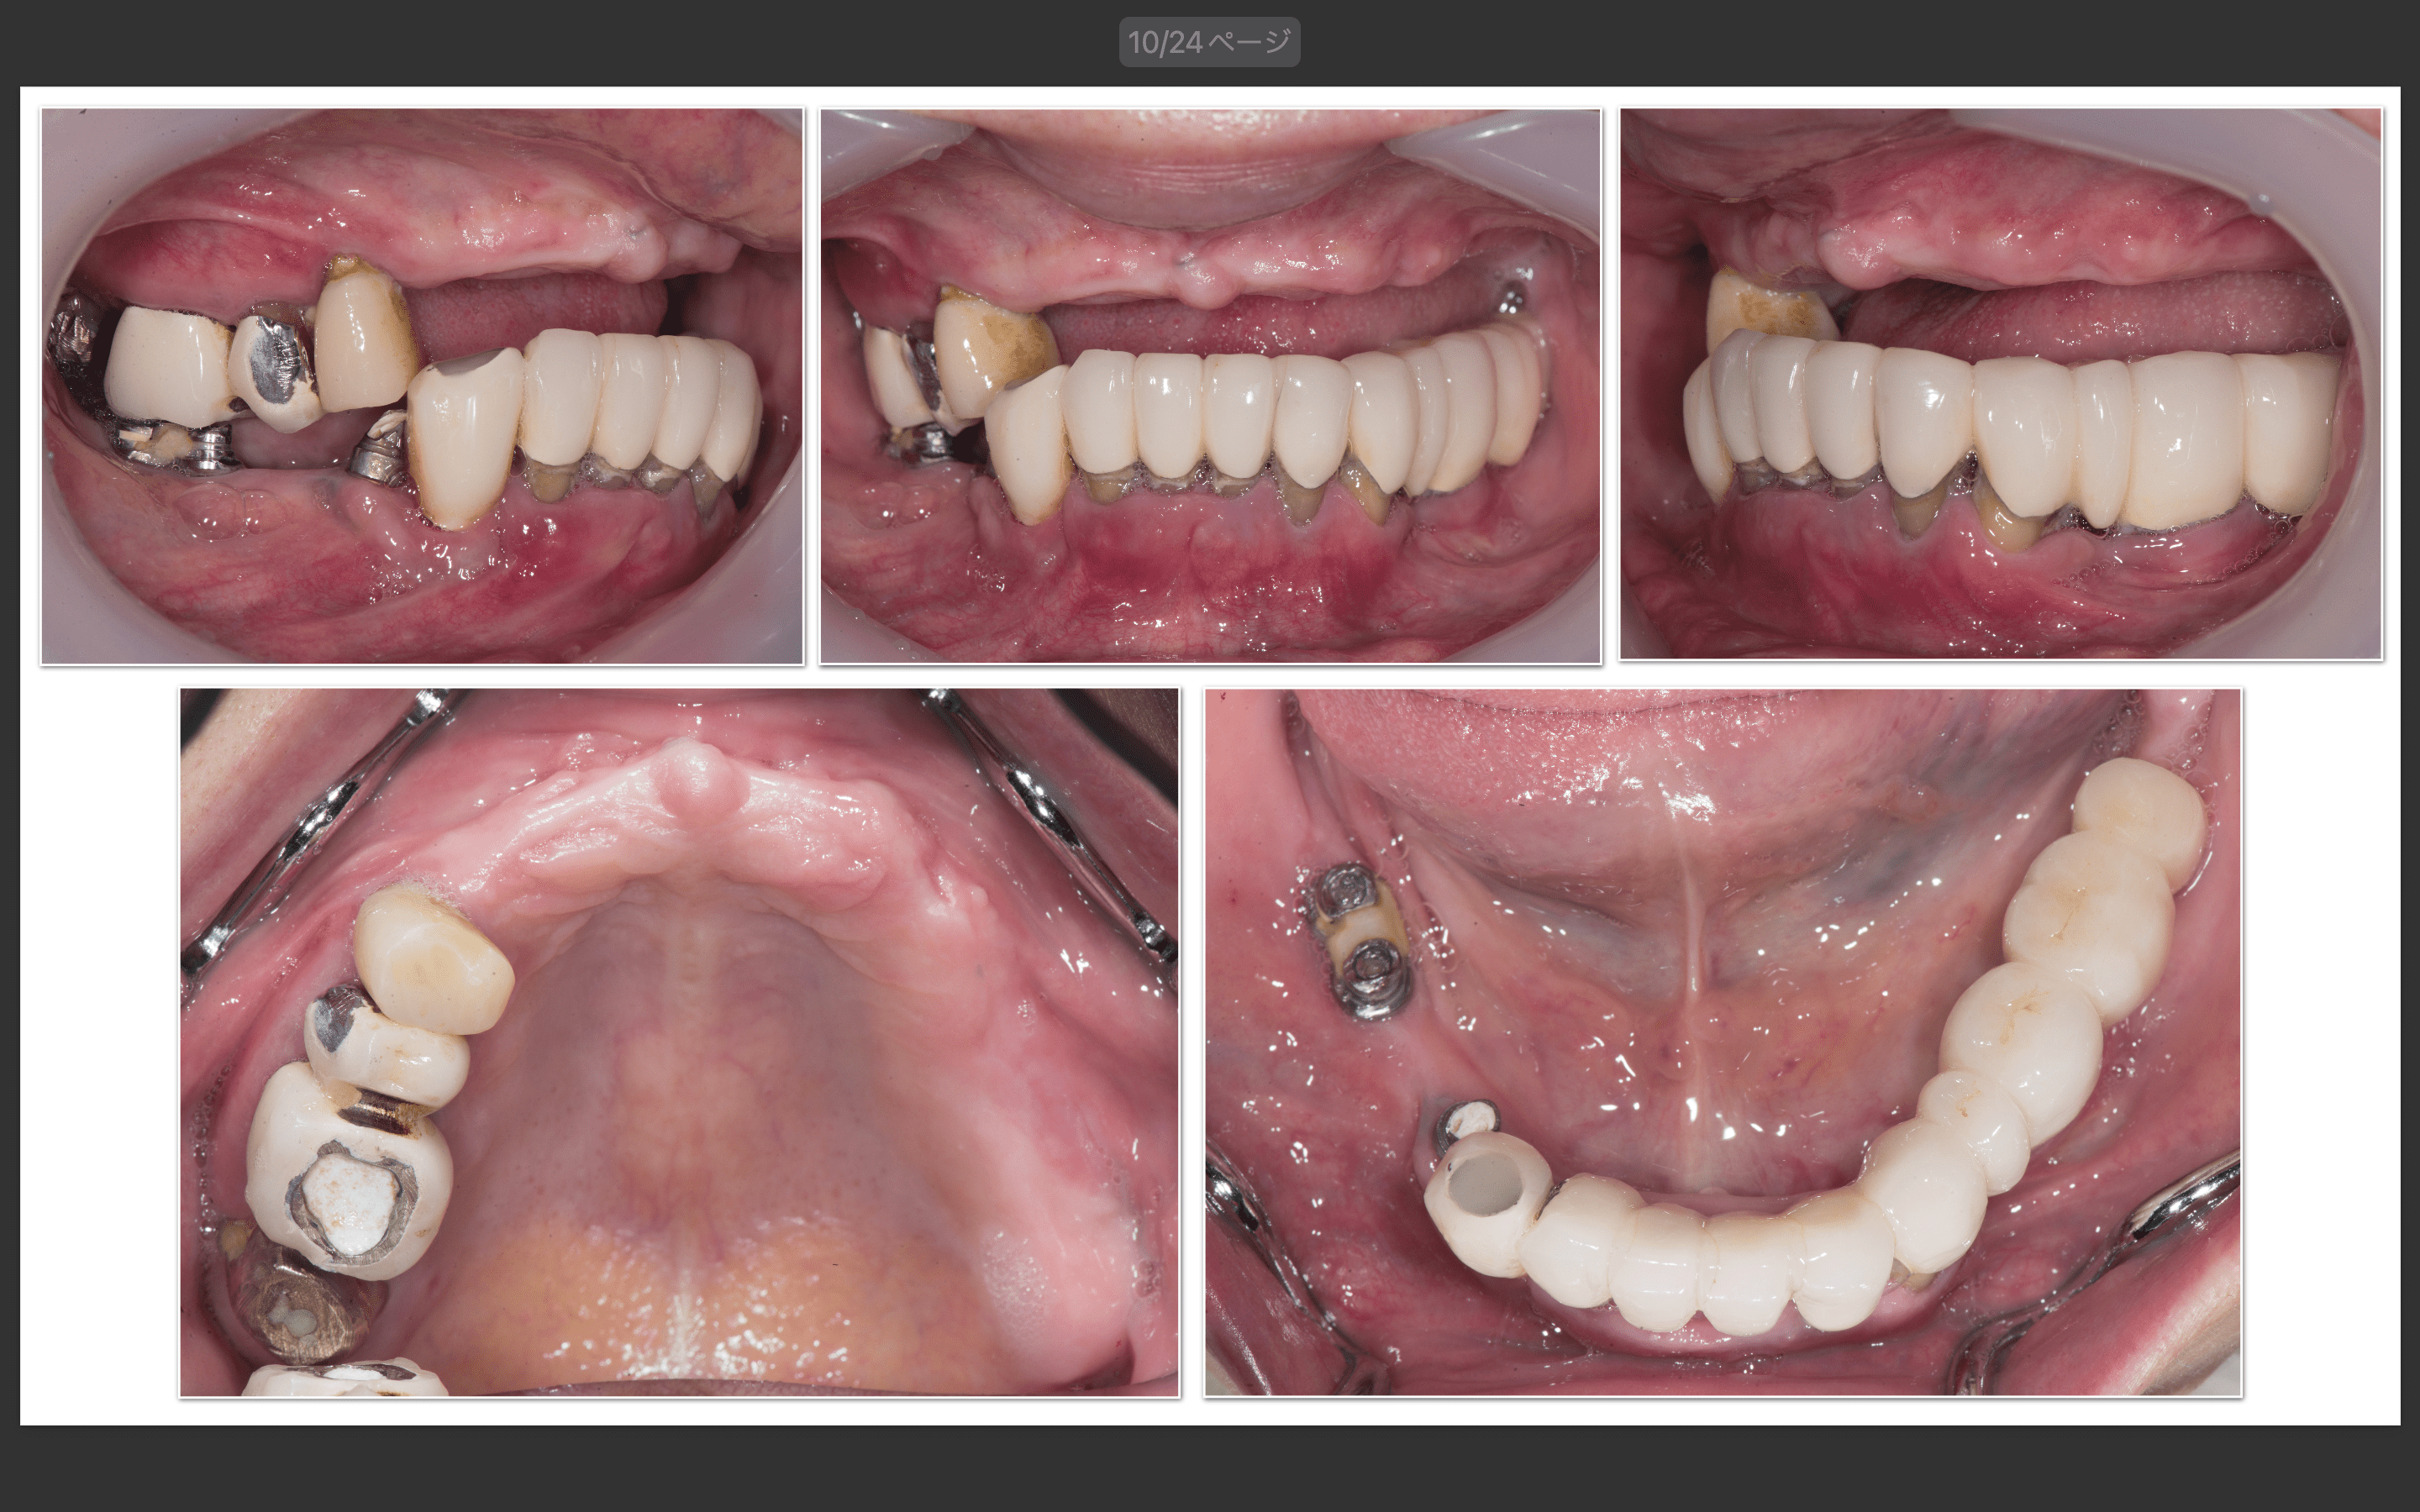

症例紹介28:オールオンシックス(All-on-6)インプラント治療《60代女性》

治療内容:現在他院で右上の根の治療をしているが、全体的に噛めないので治療を希望され来院。

上顎:虫歯がひどく、保存不可能な状態である。

下顎:インプラントが入っているが、被せ物がなずれたまま放置になっている。

上顎:根の病気と虫歯で保存不可のな状態。

下顎:インプラントが不適切な位置に入っており、撤去が必要な状態。

最終補綴

上顎:両側サイナスリフト後のロケーターアバットメントによる金属床ブリッジ

下顎:All-on-6によるフルジルコニアブリッジ

治療期間:約1年半

治療費:¥6,200,000(税込)

リスク:上顎のロケーターアバットは定期的に交換が必要です。また、上顎の人工歯が減ってきますので、定期的なメンテナンスが重要です。